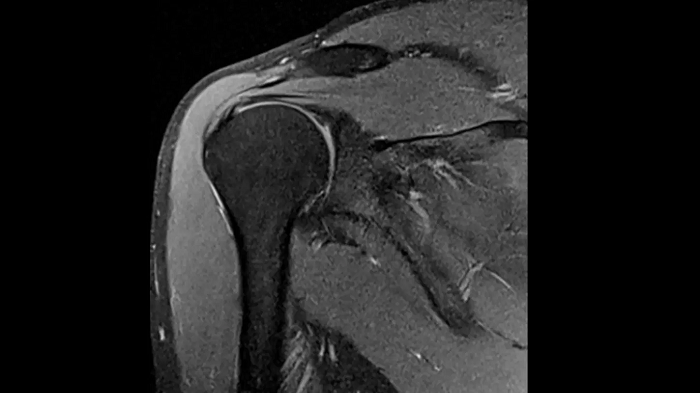

Shoulder

PD TSE Fat Sat with Deep Resolve and Simultaneous Multi-Slice

Exceptional fat suppression and performance for the shoulder’s clear imaging. Integrating the Deep Resolve’s power with the proven Simultaneous Multi-Slice technique.

SMS 2 | Deep Resolve Gain & Sharp

0.4 x 0.4 x 3.0 mm2

TA 3:20 minutes

MAC-ID: 7aaaa0213. Image Credit: Siemens Healthineers

T1 TSE with Deep Resolve and Simultaneous Multi-Slice

Outstanding T1 imaging of the shoulder using MAGNETOM Free.Star. Integrating the Deep Resolve’s power with the proven Simultaneous Multi-Slice technique.

TA 3:37 minutes